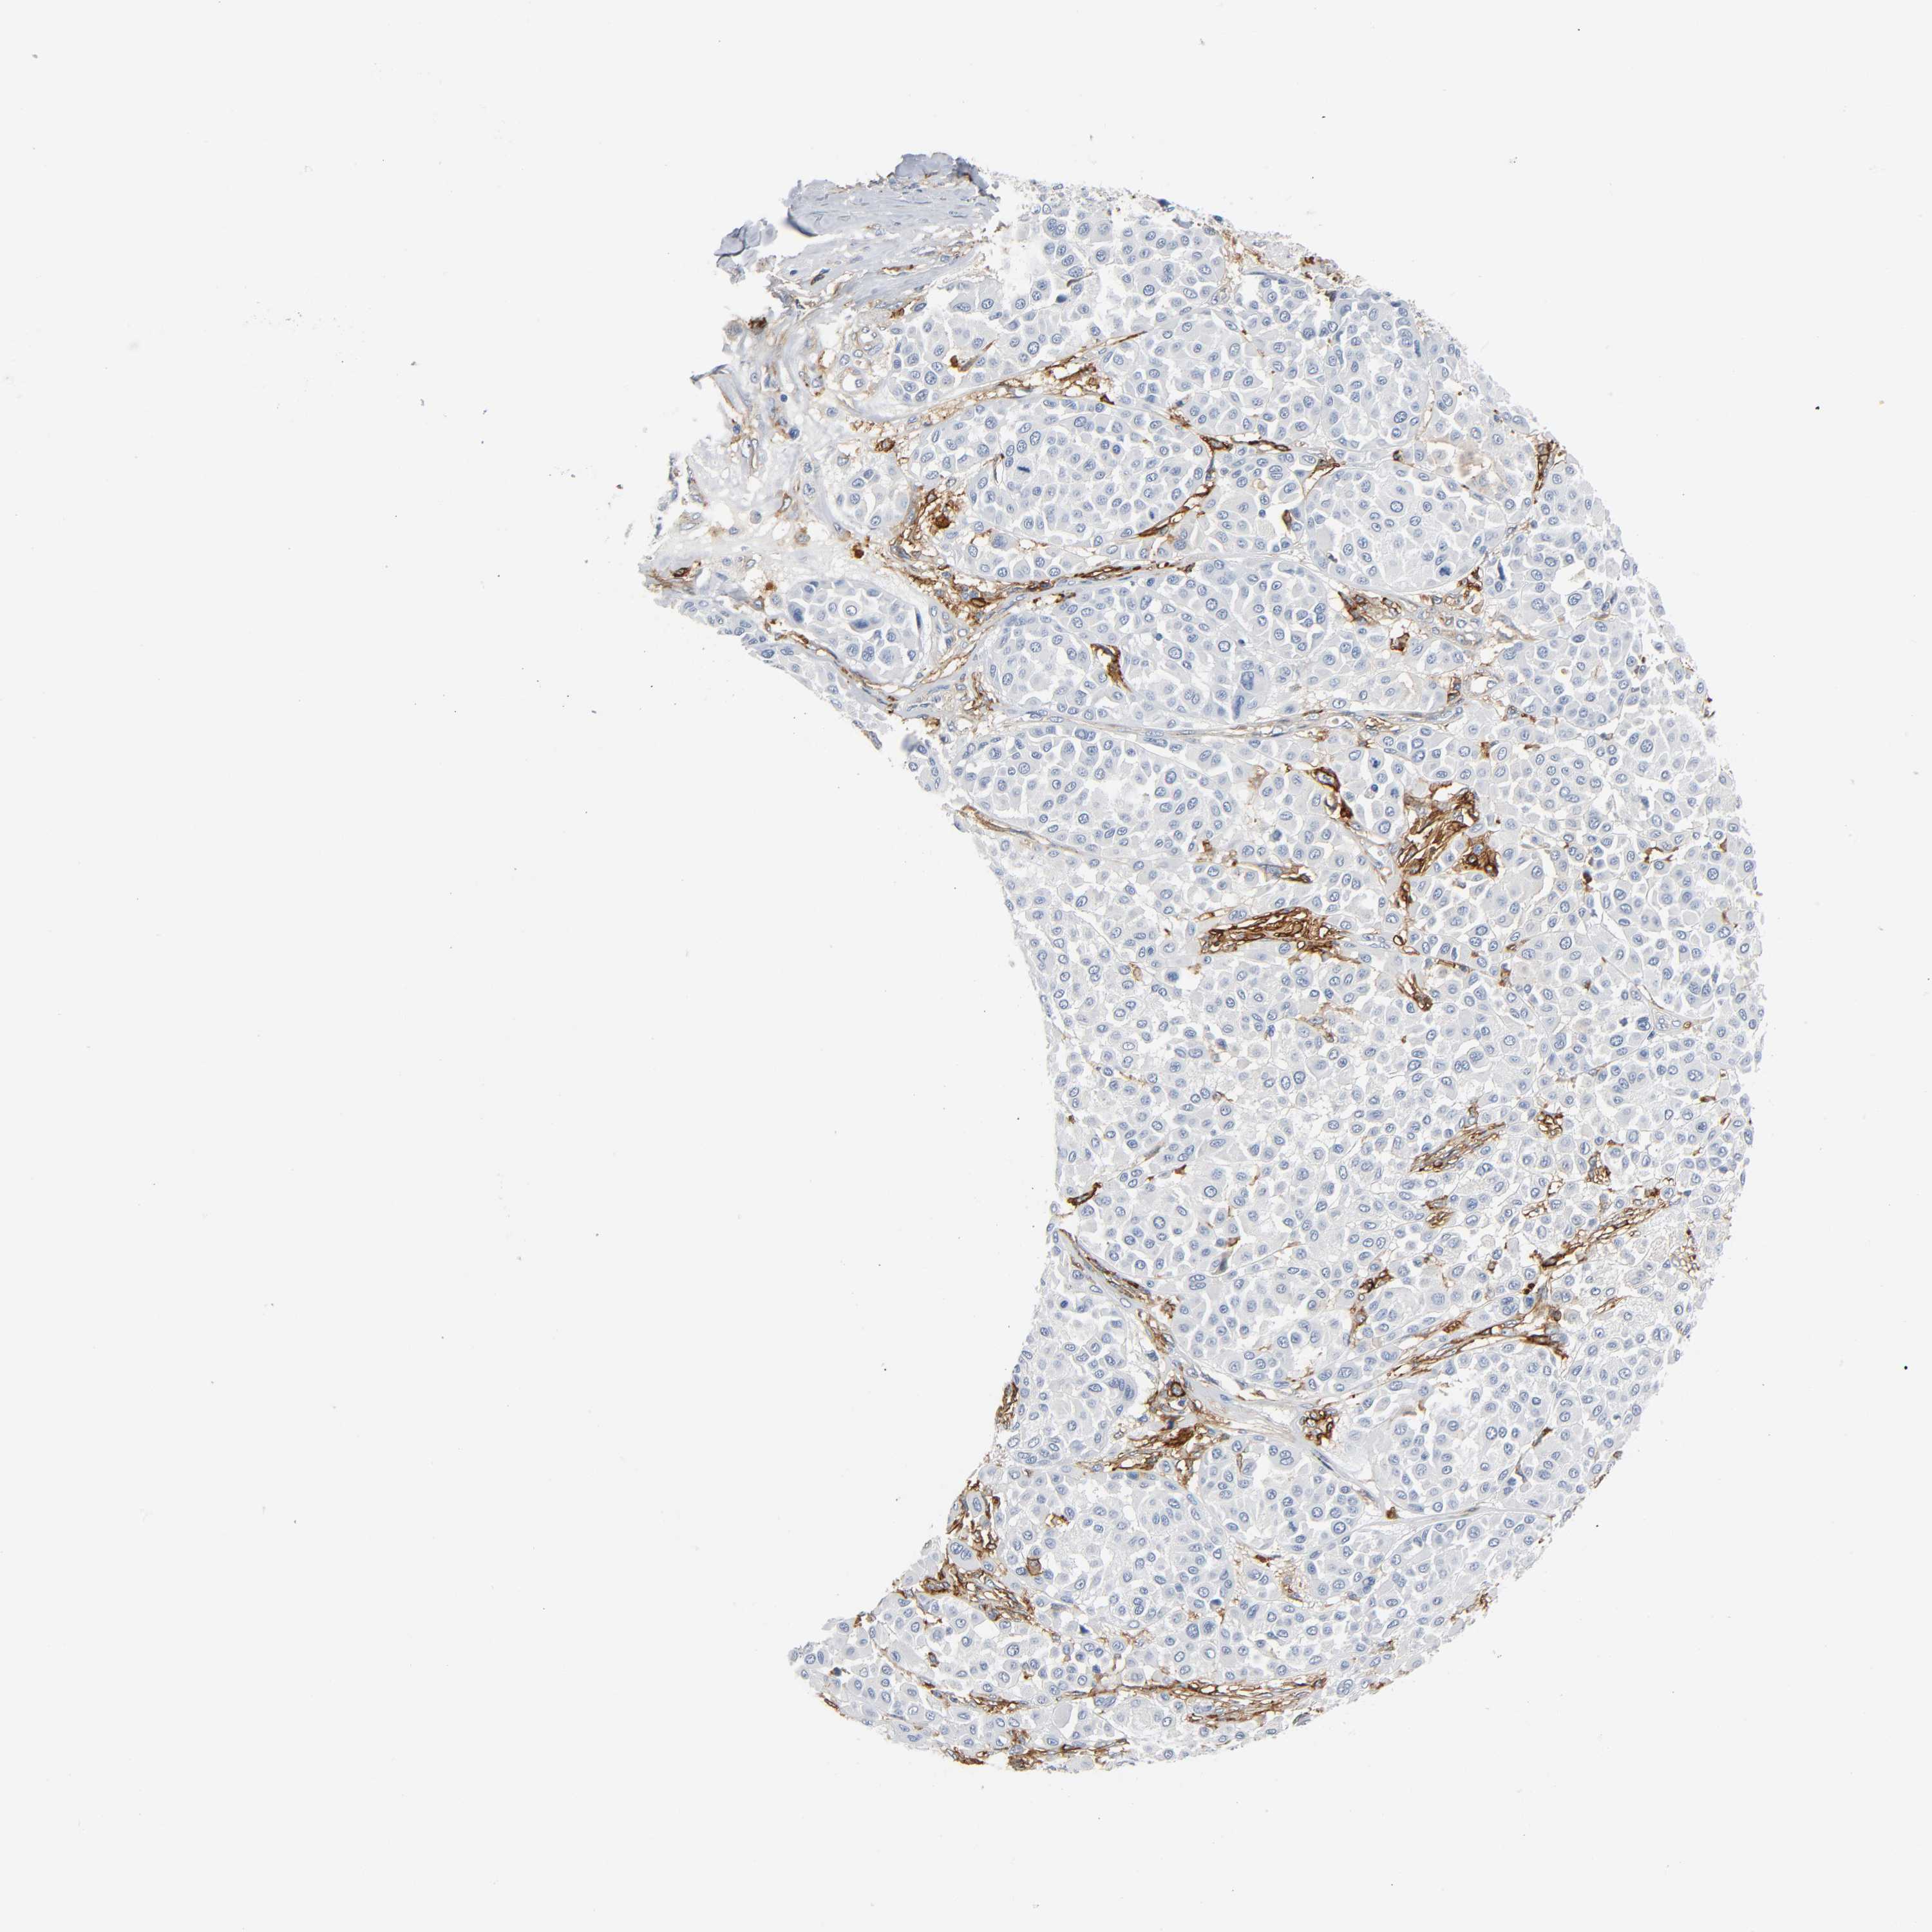

MELANOMA - Protein expressioni

A mouse-over function shows sample information and annotation data. Click on an image to view it in a full screen mode. Samples can be filtered based on level of antibody staining by selecting one or several of the following categories: high, medium, low and not detected. The assay and annotation is described here.

Note that samples used for immunohistochemistry by the Human Protein Atlas do not correspond to samples in the TCGA dataset.

Antibody stainingi

Antibody staining in the annotated cell types in the current human tissue is reported as not detected, low, medium, or high, based on conventional immunohistochemistry profiling in selected tissues. This score is based on the combination of the staining intensity and fraction of stained cells.

Each image is clickable and will lead to virtual microscopy that enables deeper exploration of all samples and also displays staining intensity scores, fraction scores and subcellular localization as well as patient and tissue information for each sample.

Antibody HPA004625

Antibody CAB002417

Staining

High

Medium

Low

Not detected

Intensity

Strong

Moderate

Weak

Negative

Quantity

>75%

75%-25%

<25%

None

Location

Nuclear

Cytoplasmic/membranous

Cytoplasmic/membranous,nuclear

Malignant melanoma, NOS

Malignant melanoma, Metastatic site